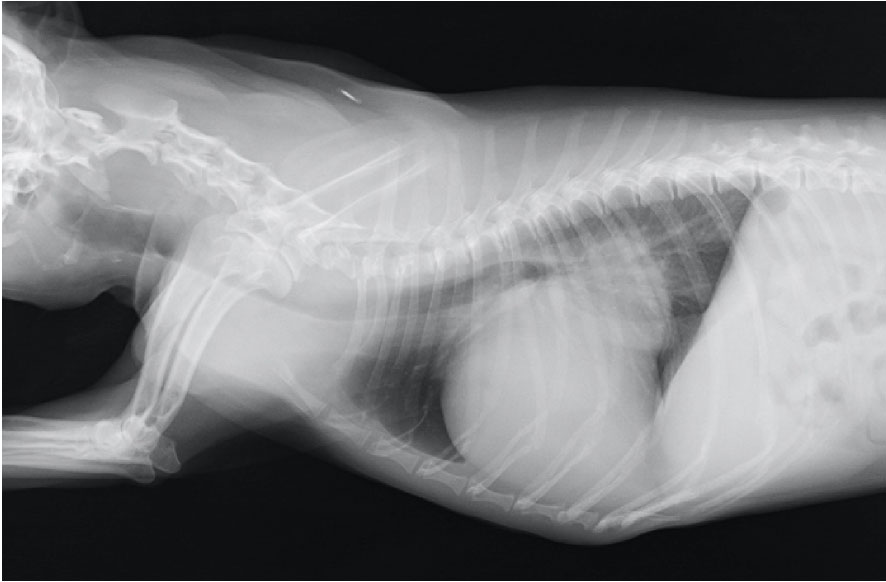

結紮前

| 犬種 | ミニチュアダックスフント 3ヶ月 2.7kg 雌 |

| 初診時の症状 | 軽度の咳と運動後に呼吸が速くなるとのことで来院。身体検査では、連続性雑音が聴取されたため,心臓エコー検査を実施。 動脈管開存症(左-右短絡)と診断しました。 |

| 治療と経過 | 左側第4肋間開胸による動脈管結紮術を実施し,術後は集中治療室で酸素管理や投薬治療を行いました。順調に回復し、呼吸状態も安定。退院後は活発に動きまわり,元気に生活しています。 |